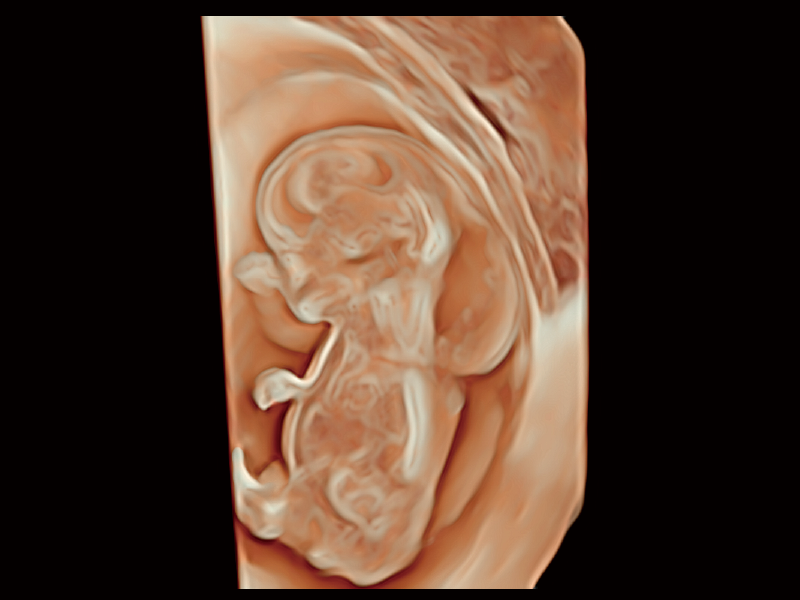

作為開立醫(yī)療全新打造的超高端旗艦超聲產(chǎn)品,從探頭抬起喚醒開啟掃查到多維探頭發(fā)射接收,通過先進(jìn)的場(chǎng)成像發(fā)射、自適應(yīng)聚合重建等技術(shù),基于RF Data原始射頻數(shù)據(jù)在圖像生成、高端功能等方面實(shí)現(xiàn)突破,為婦產(chǎn)科、兒科提供全方位臨床解決方案。